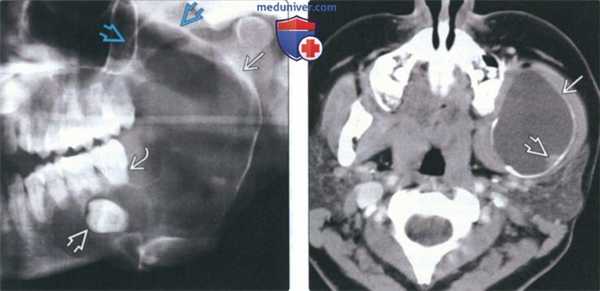

(Слева) На панорамной рентгенограмме в нижней челюсти слева определяется крупная у ни кистозная амелобластома, хорошо отграниченная кортикальной пла стинкой на периферии. Амелобластома выглядит многокамерной из-за фестончатых краев. Обратите внимание на вовлечение венечного отростка. Также определяется смещение треть его моляра с резорбцией корня.

(Справа) На аксиальной КТ с КУ у этого же пациента определяется вздутие кортикальных пластинок. Низкая плотность образования позволяет предположить кисту, однако контрастирующийся муральный узел является ключом к правильному диагнозу.